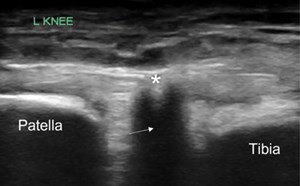

69-year old male with history of hypertension, diabetes, squamous cell carcinoma of larynx status post chemotherapy, radiation, total laryngectomy, tracheostomy dependence, and status post renal trans...